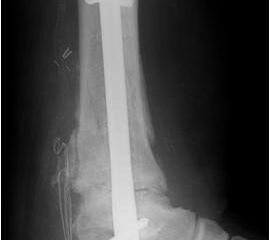

• Primäre oder posttraumatische Arthrose des OSG und USG (Abbildung 1, Abbildung 2).